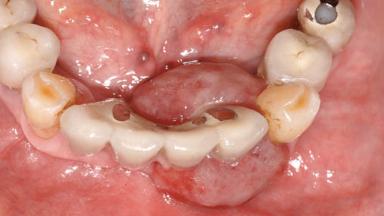

A 65-year-old female patient was referred to the periodontist for assessment and management of implant site 12. Implant 12 had been placed ten years previously and restored with a cemented single crown. The patient was a non-smoker in good general and periodontal health. On examination there were 7 mm probing depths at implant 12 with suppuration and bleeding on probing. The patient was aware of the presence of pus but had no discomfort. A periapical radiograph showed marginal bone loss to approximately the third thread of the implant. Previous radiographs obtained from the referring clinician indicated that there had been progressive bone loss since the implant was restored. A diagnosis of periimplantitis was made.